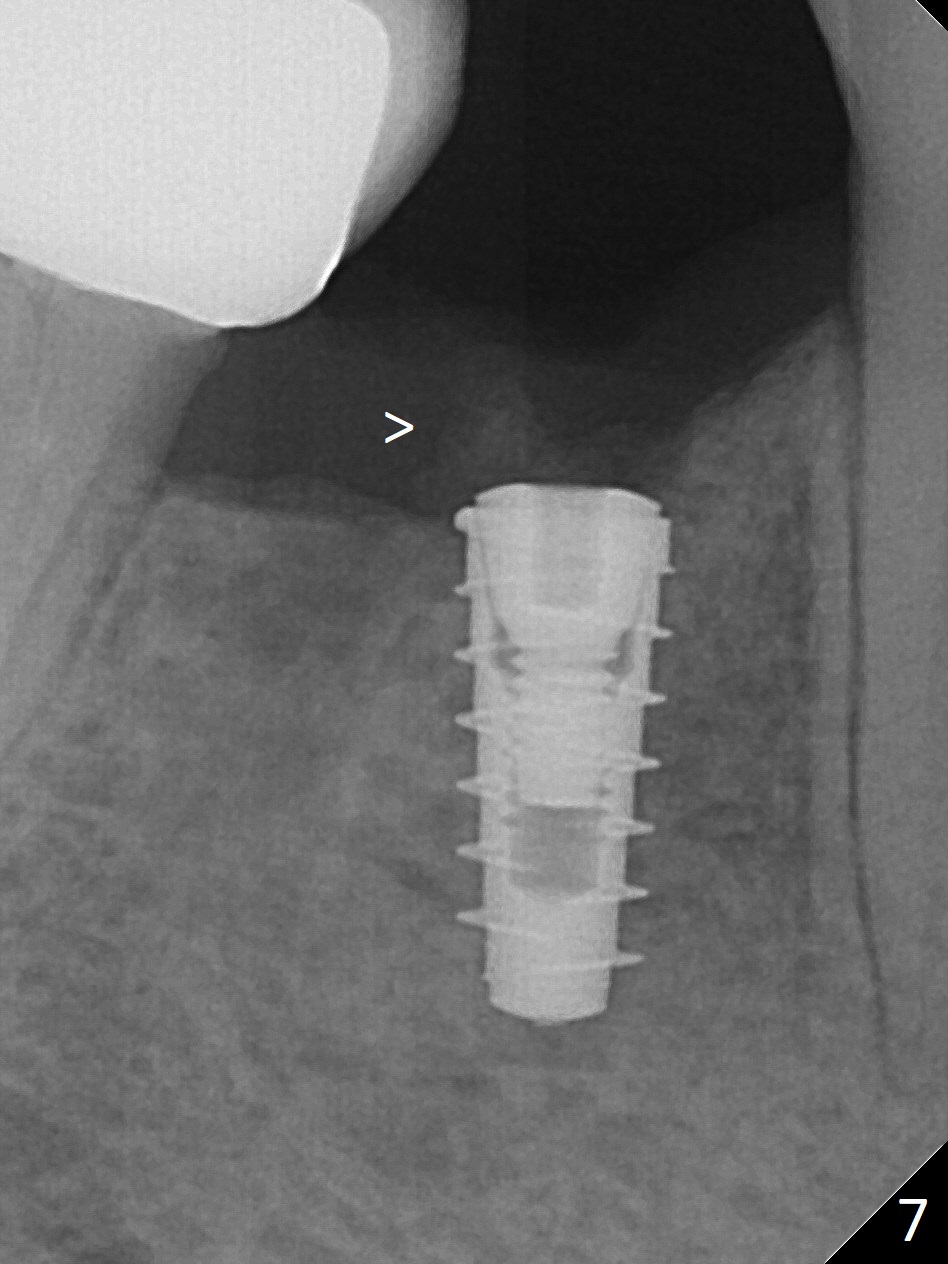

The patient returns for implant placement 11 months post extraction of #28 and 29. With flapless manner, initial osteotomy happens to drop into the original socket of #28 (Fig.4). After use of 3.3 mm Magic Drill (MD) and Final Drill for 15 mm, a 4x11 mm dummy implant is placed (Fig.5). It appears that the implant is long for the site (red dashed line: Mental Loop). However, a definitive implant (4x9 mm, IBS) has difficulty to reach its depth (Fig.6). After several rounds of untorque and retorque, the implant does not seat completely (Fig.7, implant driver disengagement) with autogenous bone placed distal (>). Retrospectively, a larger MD should have been used (3.8 mm) for complete seating in the dense bone. In fact she is post breast cancer treatment with 50% chance of relapse. The patient returns for follow up 1.5 months postop (Fig.8). The wound has healed. Impression is taken 5 months postop (Fig.9). When the crown is cemented, food impaction is an issue between the implant crown and crown at #30. Since the tooth #30 is mesially tilted with distal open margin and apical infection, the tooth will be extracted. Osteotomy is going to be initiated in the mesial slope of the mesial socket (Fig.9 red line). An implant will be placed more or less in the mesial socket (green box).